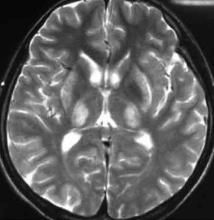

(4)腦影像學檢查:CT可顯示雙側豆狀核對稱性低密度影。MRI比CT特異性更高,表現為豆狀核(尤其殼核)、尾狀核、中腦和腦橋、丘腦、小腦及額葉皮質T1加權像低信號和T2加權像高信號,或殼核和尾狀核在T2加權像顯示高低混雜信號,還可有不同程度的腦溝增寬、腦室擴大等。